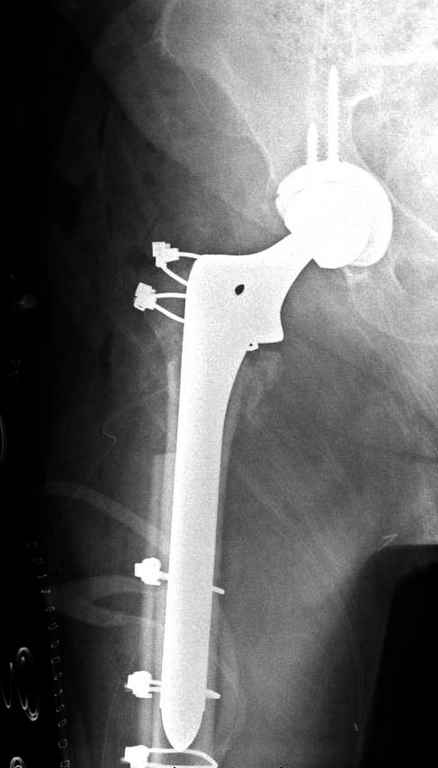

Вашему вниманию представляется похожий случай, пациентке 70, осложнился в течение одного месяца после операции. Ревизия с заменой сустава, кабельная фиксация на трохантер. При установке в дистальном диафизе обнаружен тонкий кортикальный слой и сделана профилактика от возможного перелома аллографтом.